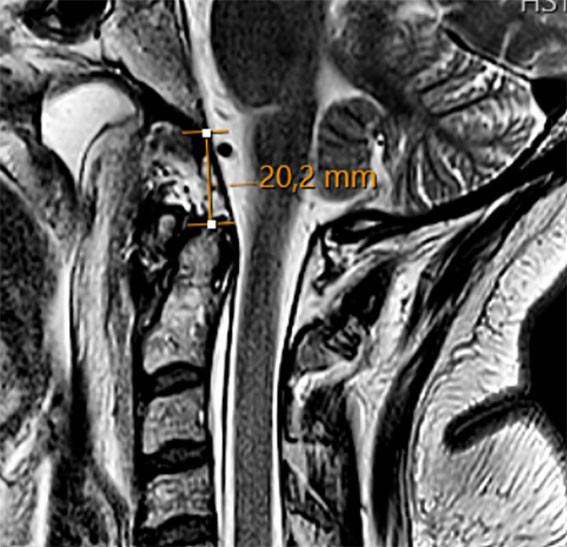

CT-undersøkelse av nakkesøylen viste en avulsjonsfraktur ved venstre oksipitalkondyl med translasjon og økt leddspalte i atlanto-oksipitalleddet – målt til 5,5 mm på venstre og 4,6 mm på høyre side (normalverdi < 1,5 mm (1)) (figur 1). Basion-dens-avstanden (BDI) ble målt til 20,2 mm (normalverdi < 8,5 mm (2)) (figur 2). Undersøkelse med magnetisk resonans (MR)-avbildning av nakkesøylen ble utført for nærmere vurdering av ligamentære strukturer, plassforhold for ryggmargen og for å kartlegge eventuelle tilleggsskader. Undersøkelsen viste uttalt prevertebral bløtvevshevelse og en ventral epidural væskeansamling uten tegn til kompresjon av ryggmargen. Det ble ikke påvist patologiske signalforandringer i ryggmargen. Alarligamentene lot seg ikke visualisere, noe som tydet på betydelig skade. På bakgrunn av bildefunnene stilte man diagnosen ustabil kraniocervikal dissosiasjon (craniocervical dissociation, CCD), klassifisert som type 2 i Traynelis-klassifikasjonen for atlanto-oksiptale dislokasjoner (3) – en separasjon mellom skallen og øvre del av nakkesøylen.